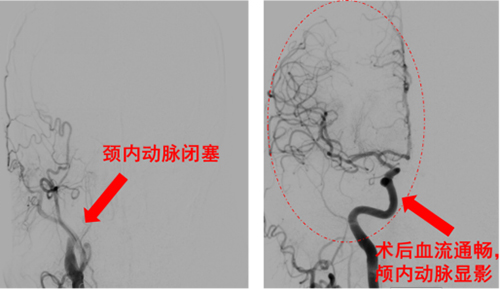

病例1——围术期卒中的精准狙击:一位62岁男性,在腰椎术后突然出现下肢活动不利并持续加重。神经外科紧急会诊,凭借敏锐的临床洞察,立即启动脑卒中一站式检查,结果揭示病因为右侧颈内急性动脉闭塞。神经外科介入团队火速行动,行急诊取栓术,成功实现颈动脉再通,颅内血流恢复显影良好。此例成功救治,彰显了我院对围术期等特殊情境下脑卒中的高效诊断与处置能力。

病例3(技术攻坚典范)——“生命通道”的极限修复:一位55岁男性,因突发左侧偏瘫、意识不清由120紧急送医。神经内科立即予以静脉溶栓,同时脑卒中一站式检查发现其右侧颈内动脉颅外段已完全闭塞,大脑面临严重缺血。神经外科介入团队在手术中遭遇了巨大挑战:患者病因并非普通血栓,而是颈动脉血管壁撕裂(夹层) 造成的闭塞,同时脱落的血栓还堵塞了大脑中动脉M2段;更棘手的是,通往病变的血管路径存在360°极度迂曲,器械通过异常困难。面对这一复杂险情,团队凭借高超的技术与丰富的经验,迎难而上。不仅将远端血栓悉数取出,更成功在颈动脉夹层部位精准植入支架,封堵破口,使夹层完美愈合,血流通畅恢复。术后患者恢复显著,意识完全清醒,并可自主下地行走。此例手术的成功,是我院在卒中介入领域实现的一项重大技术突破。